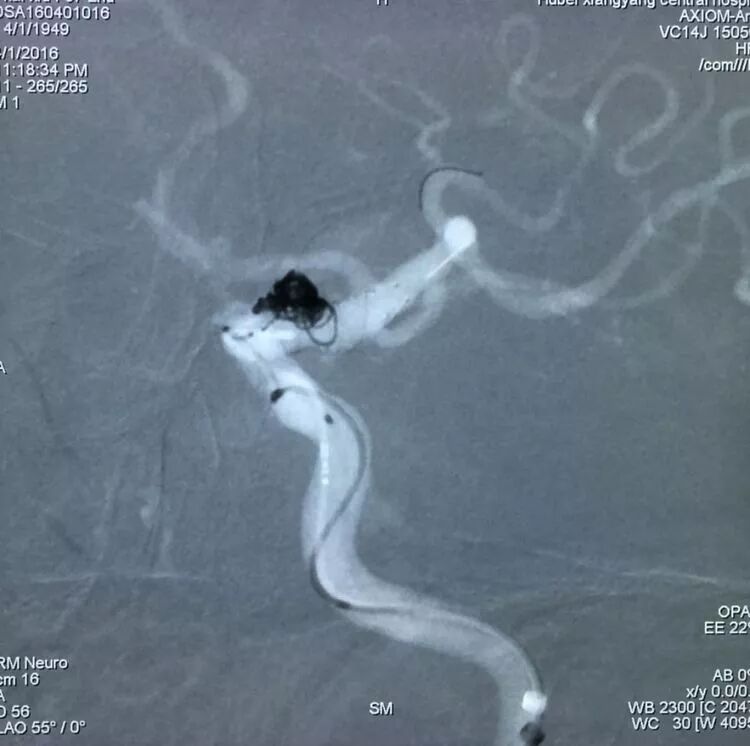

栓塞后的工作位造影和蒙片

血泡状动脉瘤,微导管头塑成Z形,应用LVIS支架结合弹簧圈完美栓塞